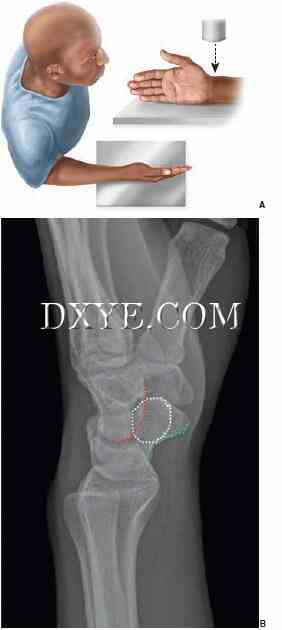

图 76.3.  手腕的标准PA射线照片。 A. 定位手腕PA射线照片。 B. 正确定位的PA视图显示了尺骨茎突桡骨的ECU凹槽。

图 76.4.  腕关节标准侧位片。 A. 手腕侧位X光片定位。 B. 一个正确定位侧视图显示豌骨(白色虚线)覆盖舟骨远(绿色虚线)和头状骨(红色虚线)。

前后位(PA)和侧位片是常规的。 PA视图是在90°外展的肩部,90°屈曲的肘关节以及中立旋转的手腕和前臂的情况下获得的(图76.3A)。 在一个真正的PA标准视图中,尺侧腕伸肌腱的沟槽应位于尺骨茎突基部的水平或径向(图76.3B)。 肩关节90°内收,肘关节屈曲90°,手与肱骨相同(图76.4A)。 在真正的侧面图中,豌豆皮的掌侧皮层应覆盖远侧舟骨掌侧皮质和头状体头部之间的中间三分之一(图76.4B)。